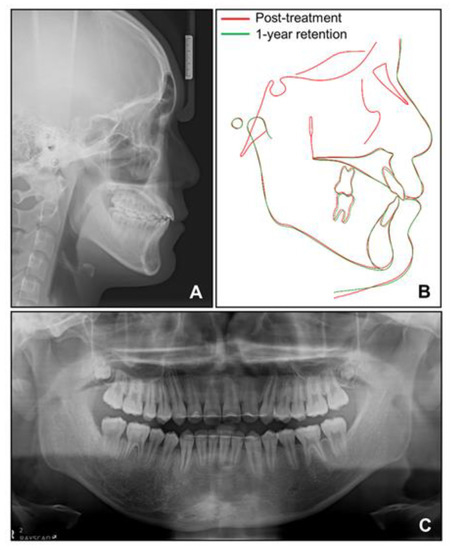

Figure 5. Radiographs after phase 1 treatment. (A) Lateral cephalogram; (B) Superimposition before and after phase 1 treatment; (C) Panoramic radiograph.

Based on this, we decided to start an orthopedic treatment and closely follow up the hypertrophic region. We placed a bonded rapid palatal expansion appliance with a hook for the face mask, and the screw was turned once a day for 2 weeks. The separation of the midpalatal suture was confirmed, and the face mask was set up with the instruction of wearing it for at least 14 h a day. After 5 months, the crossbite was relieved, and the anteroposterior jaw relationship was improved. Nevertheless, there was still a lack of space for the eruption of permanent teeth on the maxillary dentition (Figure 4A). We stopped the use of the face mask and set up an active removable appliance on the maxilla to gain space. After 18 months, sufficient space was made on the maxillary dentition, and we decided to finish the phase 1 treatment (Figure 4B and Figure 5).

Cephalometric analysis showed that a skeletal Class I relationship was well-maintained after the phase 1 treatment, with an ANB of 2.5°. Both previously lingually inclined maxillary and mandibular incisors were improved to the normal range. The patient was satisfied with the results and remained stable for 1 year after debonding. While a slight relapse pattern of open bite was observed in the left anterior region, no remarkable increase in the right mandibular right hypertrophic region was observed (Figure 13 and Figure 14).